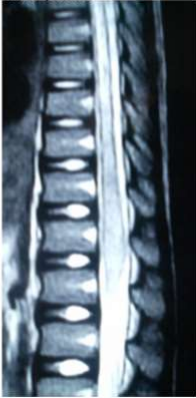

Images (4 & 5) MRI of Case No (6). Showing cauda equina expansion and hyperintense patches of in the cauda equine of both T1 and T2 weighted MRI.

Eight of the ten patients were diagnosed utilizing MRI which showed Dorsal 12 to Lumber 1 or 2 spinal cord swelling with hyper intense patches in T2 images , while the remaining two patient were diagnosed utilizing CT myelogram which showed Dorsal 12 to Lumber 1 or 2 spinal cord swelling.

Magnetic resonance imaging in spinal schistosomiasis usually shows swollen conus and epiconus beside areas of hyper-signal in T2 and heterogeneous contrast enhancement[12]. Multinodular intramedullary contrast enhancement of the distal cord allowed accurate preoperative MR imaging diagnosis of spinal schistosomiasis[12]. Cerebrospinal fluid (CSF) may show changes in spinal schistosomiasis. Characteristic features are mild to moderate pleocytosis, presence of eosinophils, slight to moderate protein increase, elevated gamma globulin concentration and a positive immune assay. These abnormalities are not always, accidentally schistosomal ovae may appear in the cerebrospinal fluid [13].